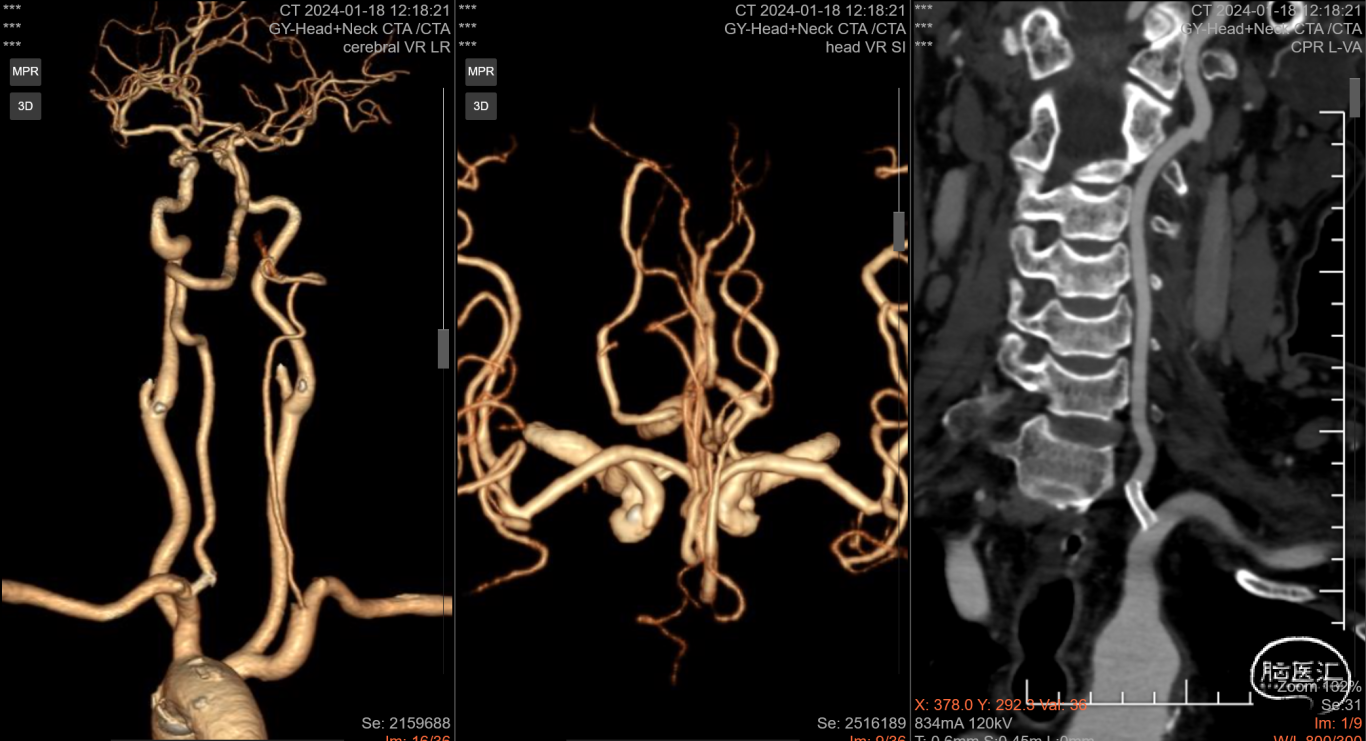

术后6天复查CTA

术前术后(6天)血管对比